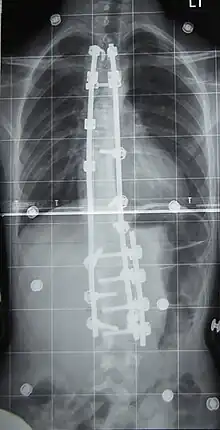

Surgery is usually recommended by orthopedists for curves with a high likelihood of progression (i.e., greater than 45–50° of magnitude), curves that would be cosmetically unacceptable as an adult, curves in people with spina bifida and cerebral palsy that interfere with sitting and care, and curves that affect physiological functions such as breathing.[102][103]

Surgery is indicated by the Society on Scoliosis Orthopaedic and Rehabilitation Treatment (SOSORT) at 45–50°[4] and by the Scoliosis Research Society (SRS) at a Cobb angle of 45°.[104] SOSORT uses the 45–50° threshold as a result of the well-documented, plus or minus 5° measurement error that can occur while measuring Cobb angles.[104]

Surgeons who are specialized in spine surgery perform surgery for scoliosis. To completely straighten a scoliotic spine is usually impossible, but for the most part, significant corrections are achieved.[105]

The two main types of surgery are:[106]

- Anterior fusion: This surgical approach is through an incision at the side of the chest wall.

- Posterior fusion: This surgical approach is through an incision on the back and involves the use of metal instrumentation to correct the curve.

One or both of these surgical procedures may be needed. The surgery may be done in one or two stages and, on average, takes four to eight hours.